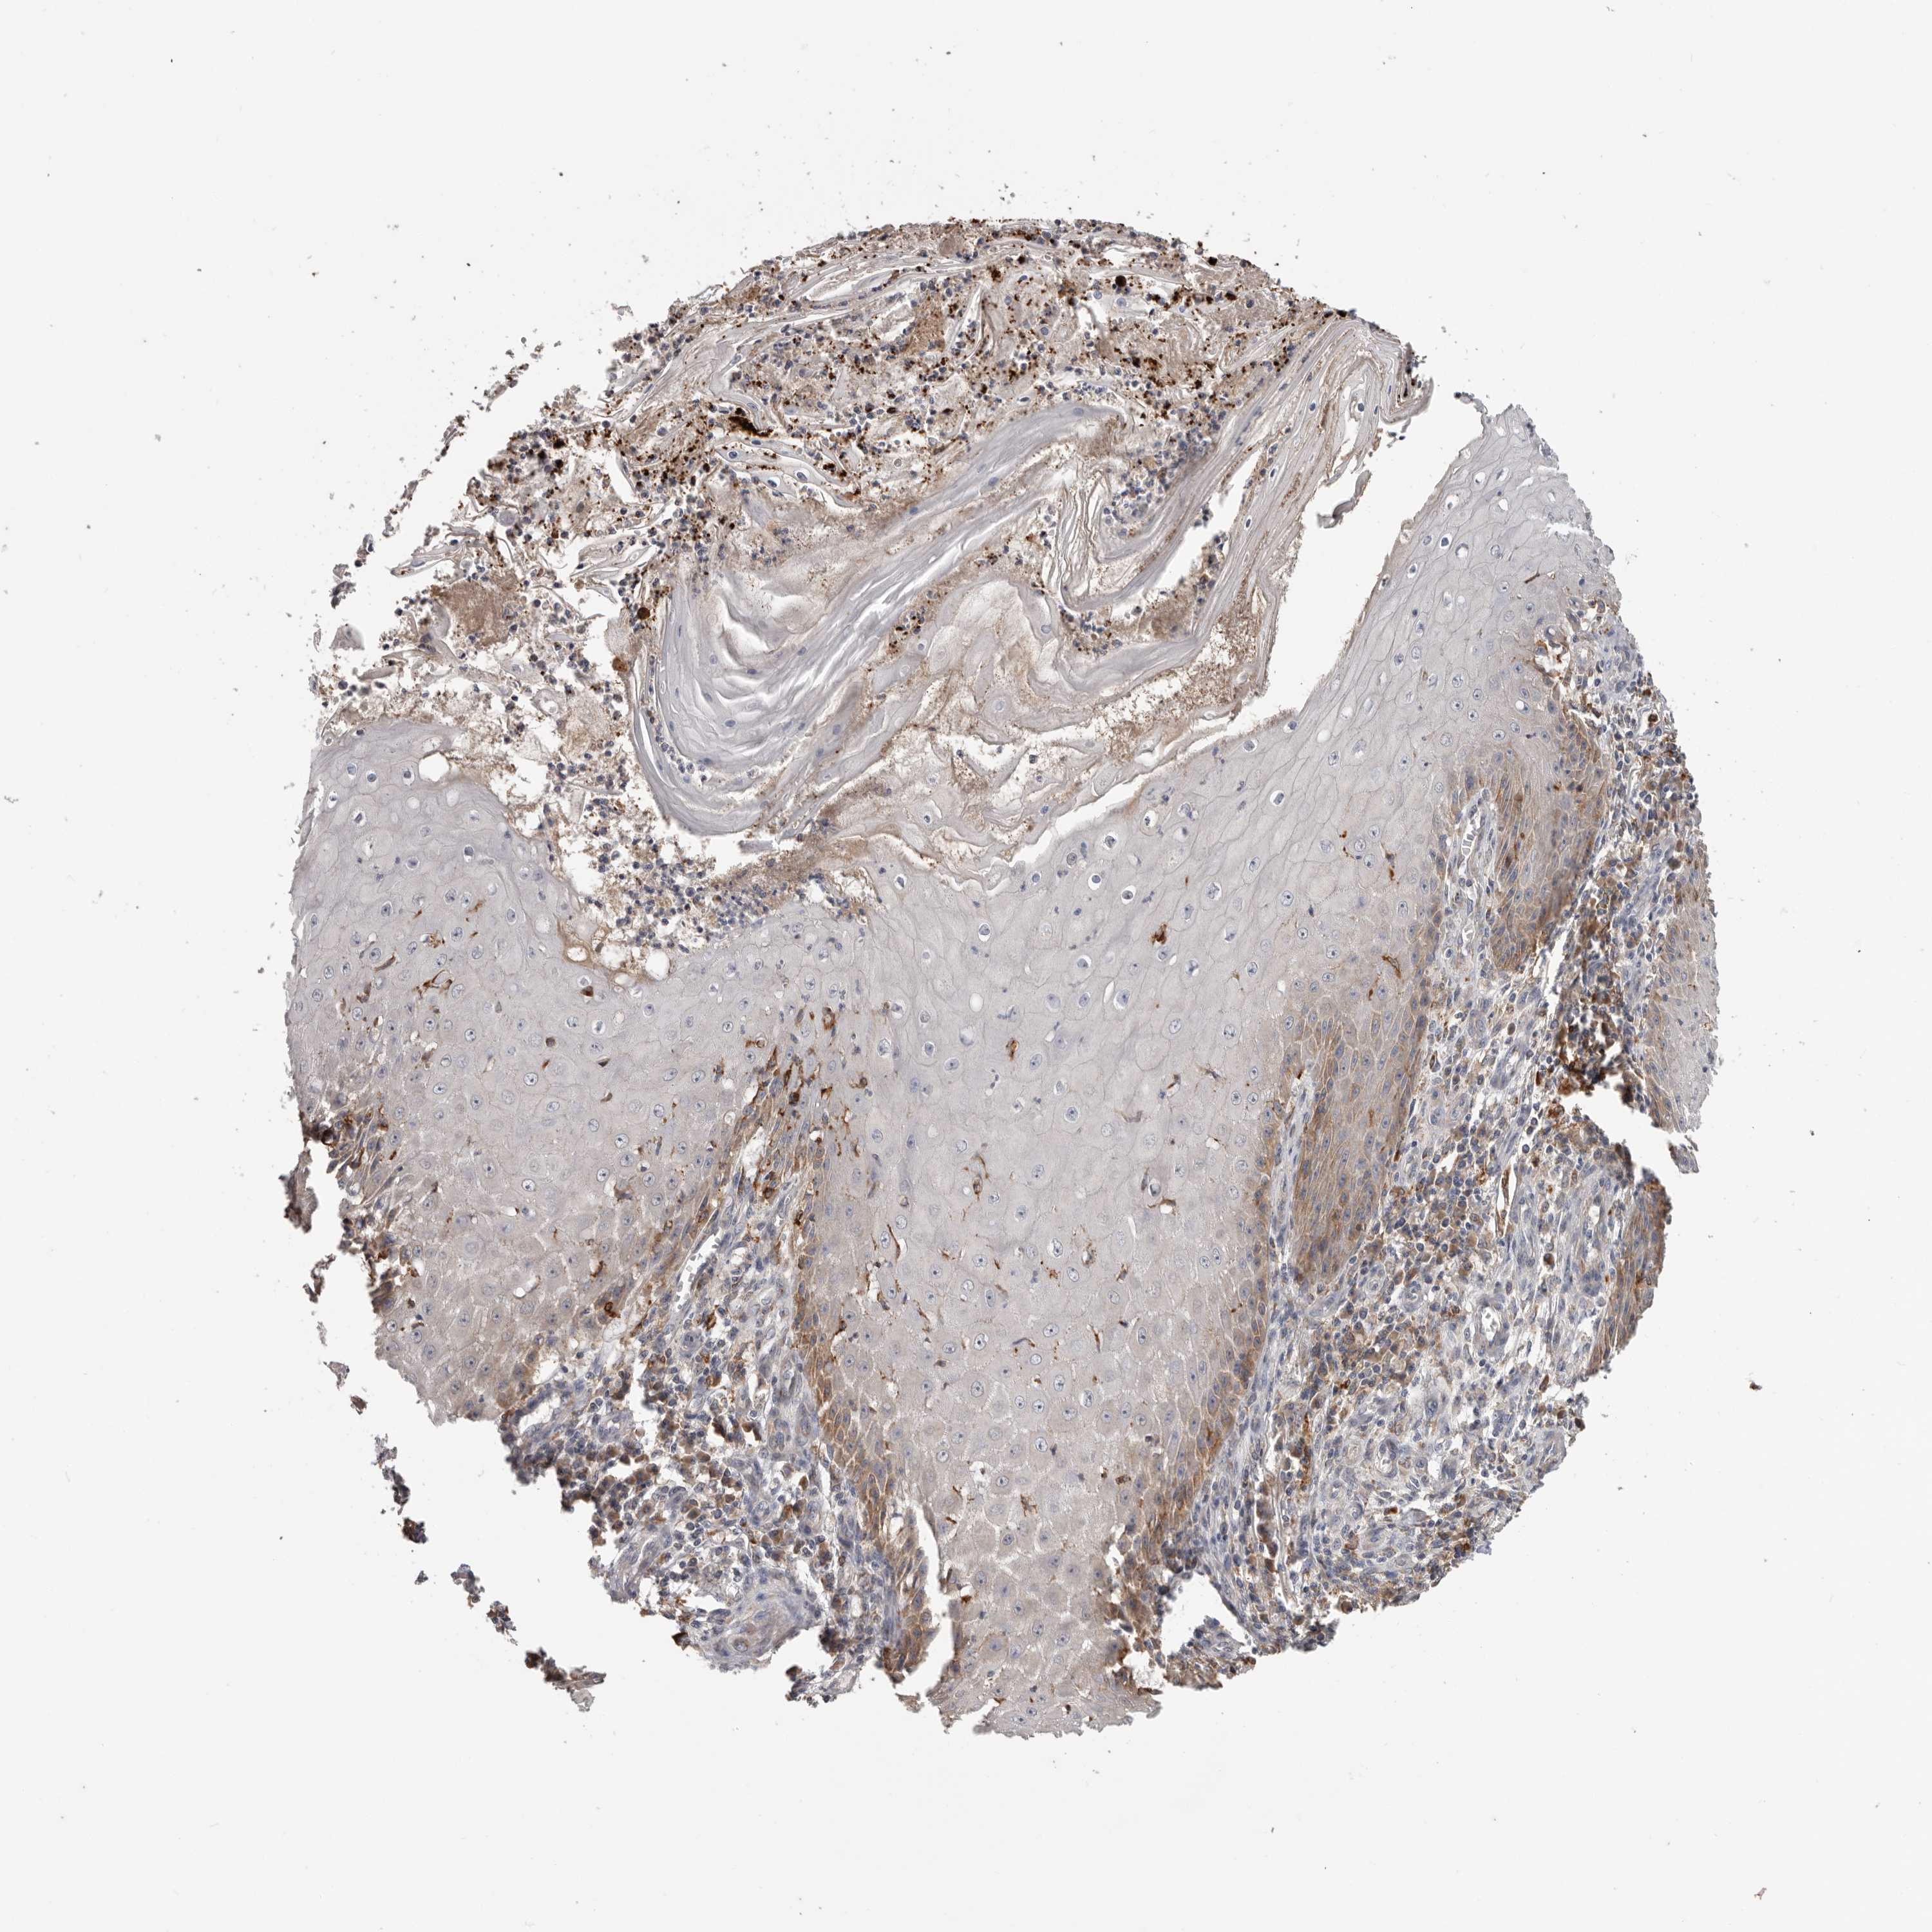

SKIN CANCER - Protein expressioni

A mouse-over function shows sample information and annotation data. Click on an image to view it in a full screen mode. Samples can be filtered based on level of antibody staining by selecting one or several of the following categories: high, medium, low and not detected. The assay and annotation is described here.

Antibody staining in the annotated cell types in the current human tissue is reported as not detected, low, medium, or high, based on conventional immunohistochemistry profiling in selected tissues. This score is based on the combination of the staining intensity and fraction of stained cells.

Each image is clickable and will lead to virtual microscopy that enables deeper exploration of all samples and also displays staining intensity scores, fraction scores and subcellular localization as well as patient and tissue information for each sample.

Antibody CAB000153

Squamous cell carcinoma, NOS